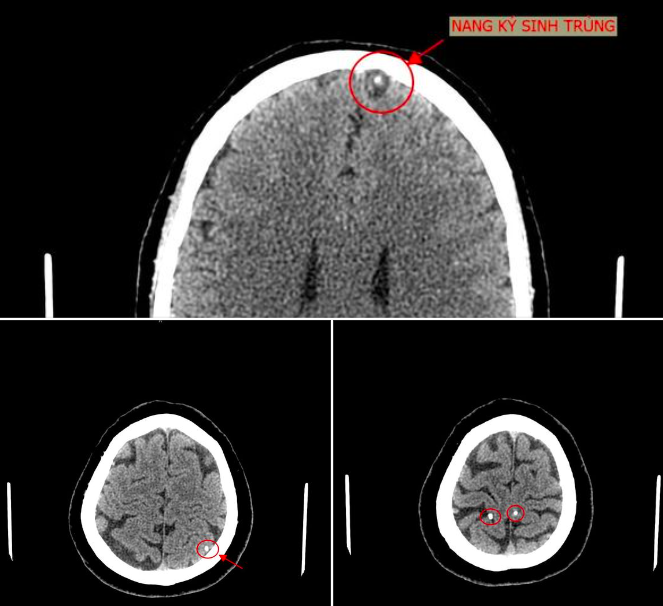

Bệnh nhân vào Trung tâm Y tế Tân Sơn (Phú Thọ) ngày 23/6. Bác sĩ khoa Chẩn đoán hình ảnh kết luận trong sọ não bệnh nhân có hình ảnh nang ký sinh trùng (ấu trùng sán não). Bệnh nhân cho biết bản thân có thói quen ăn đồ sống như gỏi cá.